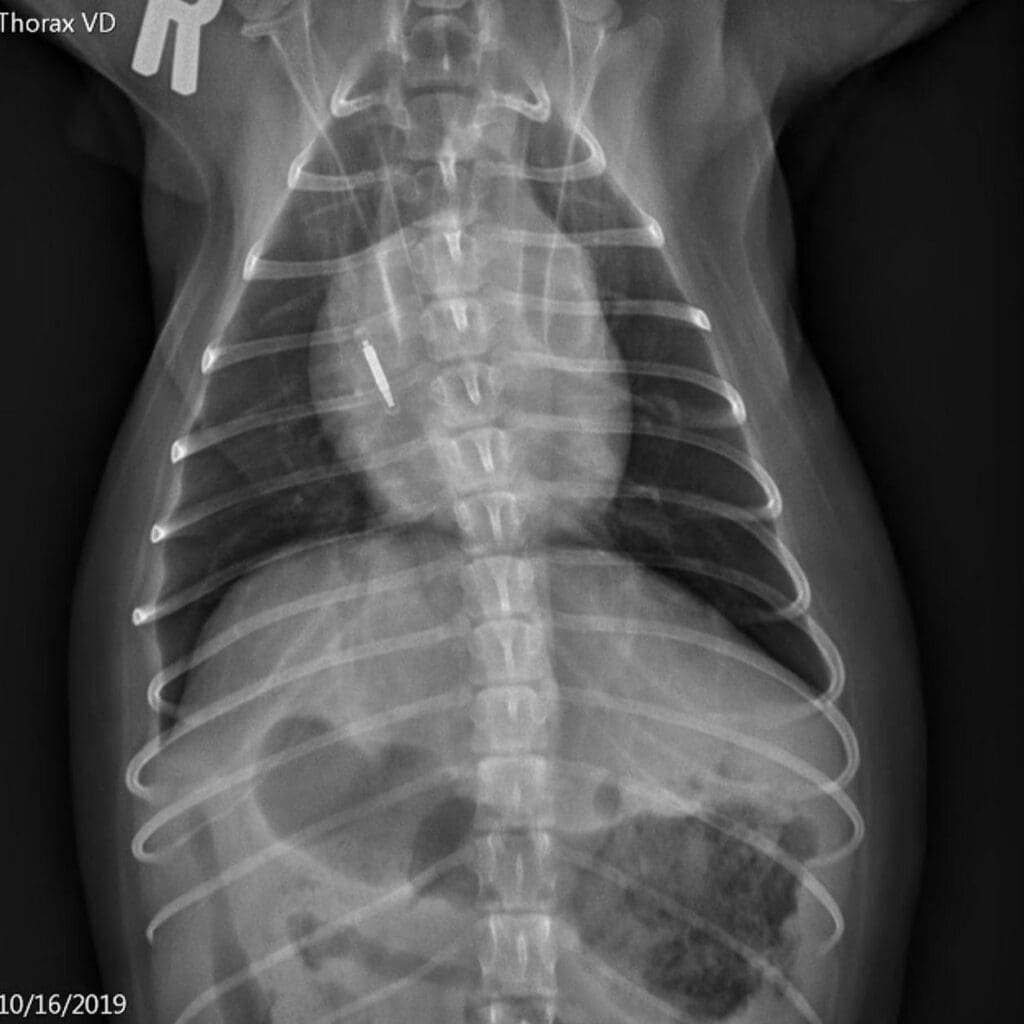

VD view of the thorax before the blood transfusion

Our patient had acutely-developed bilateral infiltrates, received a blood transfusion within 6 hours prior to the onset of clinical signs and was likely severely hypoxemic. No heart murmur or left atrial enlargement was evident on physical examination and thoracic imaging, therefore a cardiogenic origin of pulmonary infiltrates is deemed unlikely.